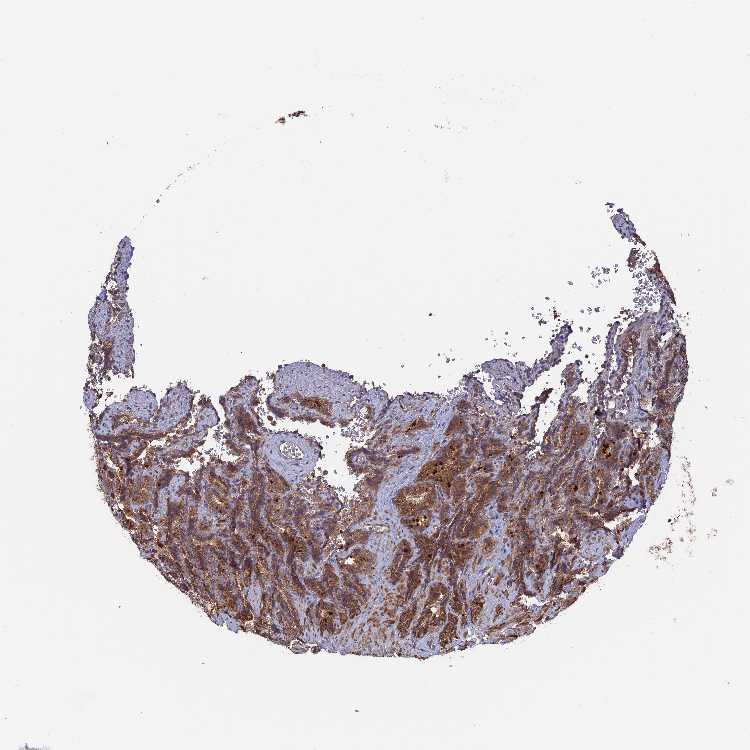

TISSUE PRIMARY DATA SEMINAL VESICLE Show tissue menu

SEMINAL VESICLE - Antibody stainingi

Antibody staining in the annotated cell types in the current human tissue is reported as not detected, low, medium, or high, based on conventional immunohistochemistry profiling in selected tissues. This score is based on the combination of the staining intensity and fraction of stained cells.

Each image is clickable and will lead to virtual microscopy that enables deeper exploration of all samples and also displays staining intensity scores, fraction scores and subcellular localization as well as patient and tissue information for each sample.

Antibody HPA041348Antibody HPA041473

Glandular cells MediumMedium